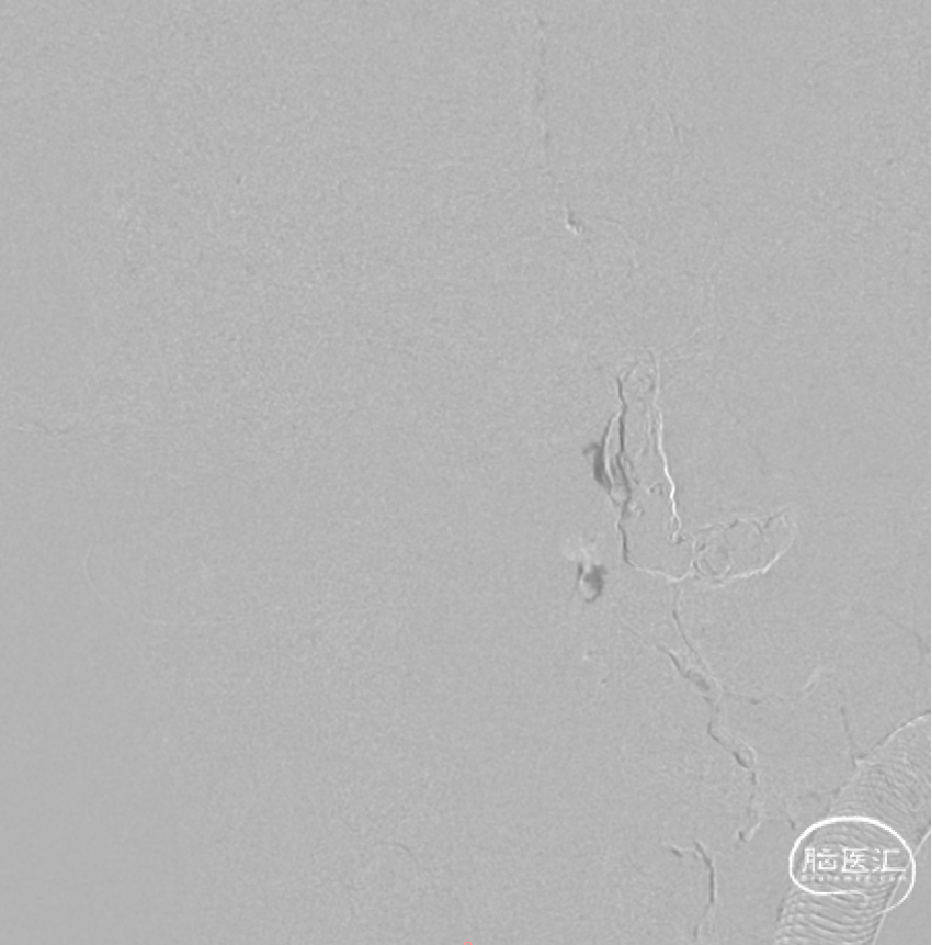

CCJ AVF完全不显影

右侧椎动脉造影CCJ AVF完全不显影,左侧PICA保护良好

左侧椎动脉造影不见CCJ AVF显影